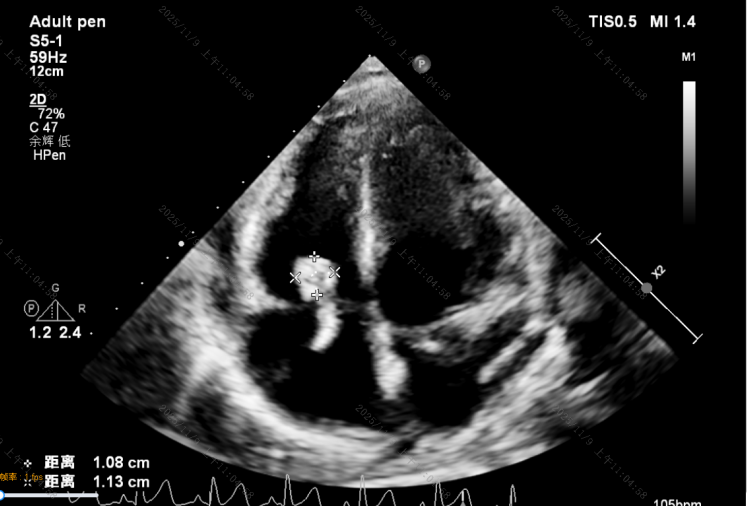

患儿因“活动后胸闷、气促1月,发热7天”入院,心脏彩超提示:先天性心脏病、室间隔缺损、感染性心内膜炎、三尖瓣多发赘生物,最大约18*12mm,累及三尖瓣前、后、隔叶,随心动周期摆动,随时可能脱落至肺动脉引起肺栓塞。经过18天规范抗感染治疗,病情得到控制,但患儿再次出现发热,心率增快。

术前超声:感染性心内膜炎致三尖瓣全瓣叶破坏及巨大赘生物附着